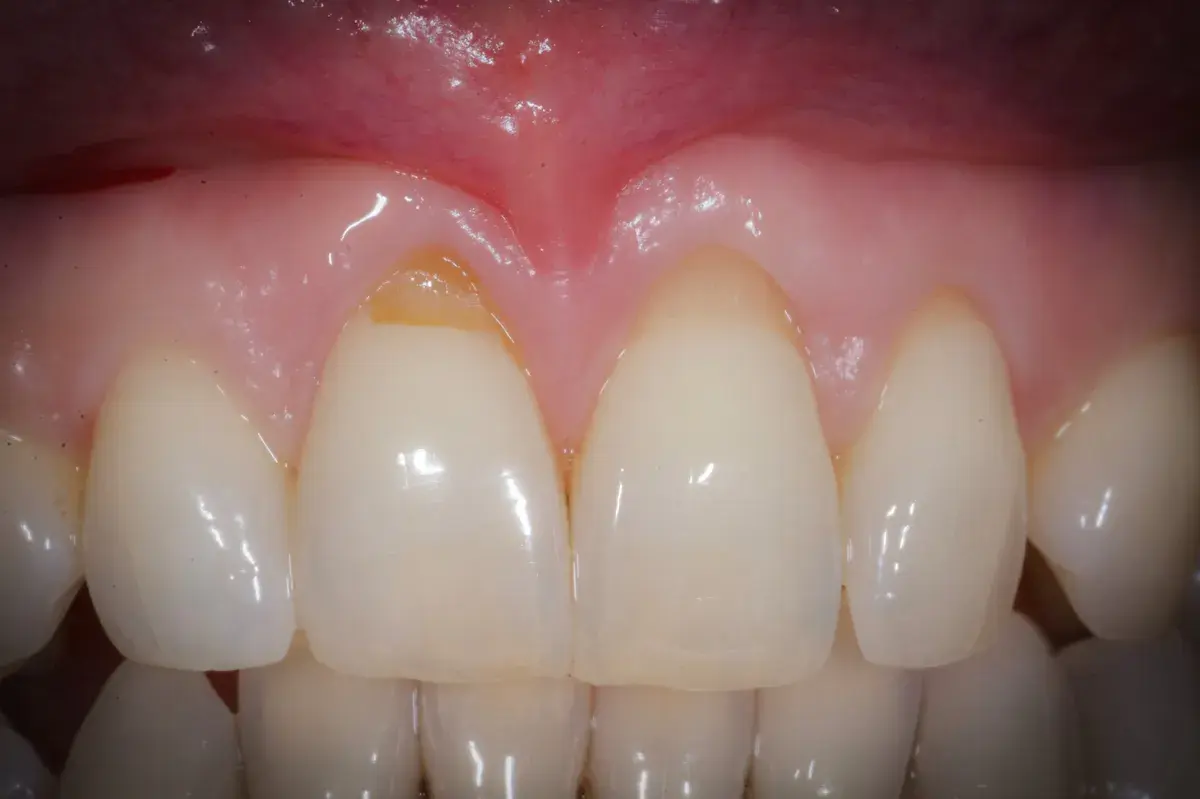

Storia vera di turismo dentale: capsule sbagliate all'estero, alitosi e infezioni. Come Manuela ha compromesso denti sani per un'illusione di risparmio.

Le recessioni gengivali possono essere corrette o meno. Esistono indicazioni assolute e relative al trattamento chirurgico con copertura radicolare.

Perché le gengive si ritirano, quando preoccuparsi e cosa può fare il parodontologo. Classificazione di Cairo, innesto connettivale, lembo coronale.